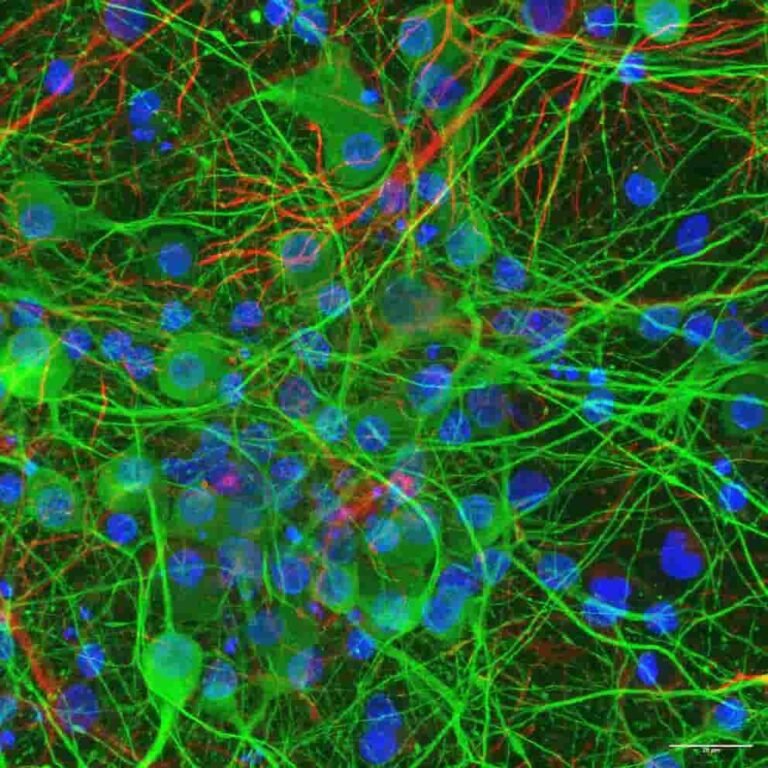

InvestigaciónVacunas e IAEnsayos, vigilancia genómica y salud digital avanzan como herramientas estratégicas.